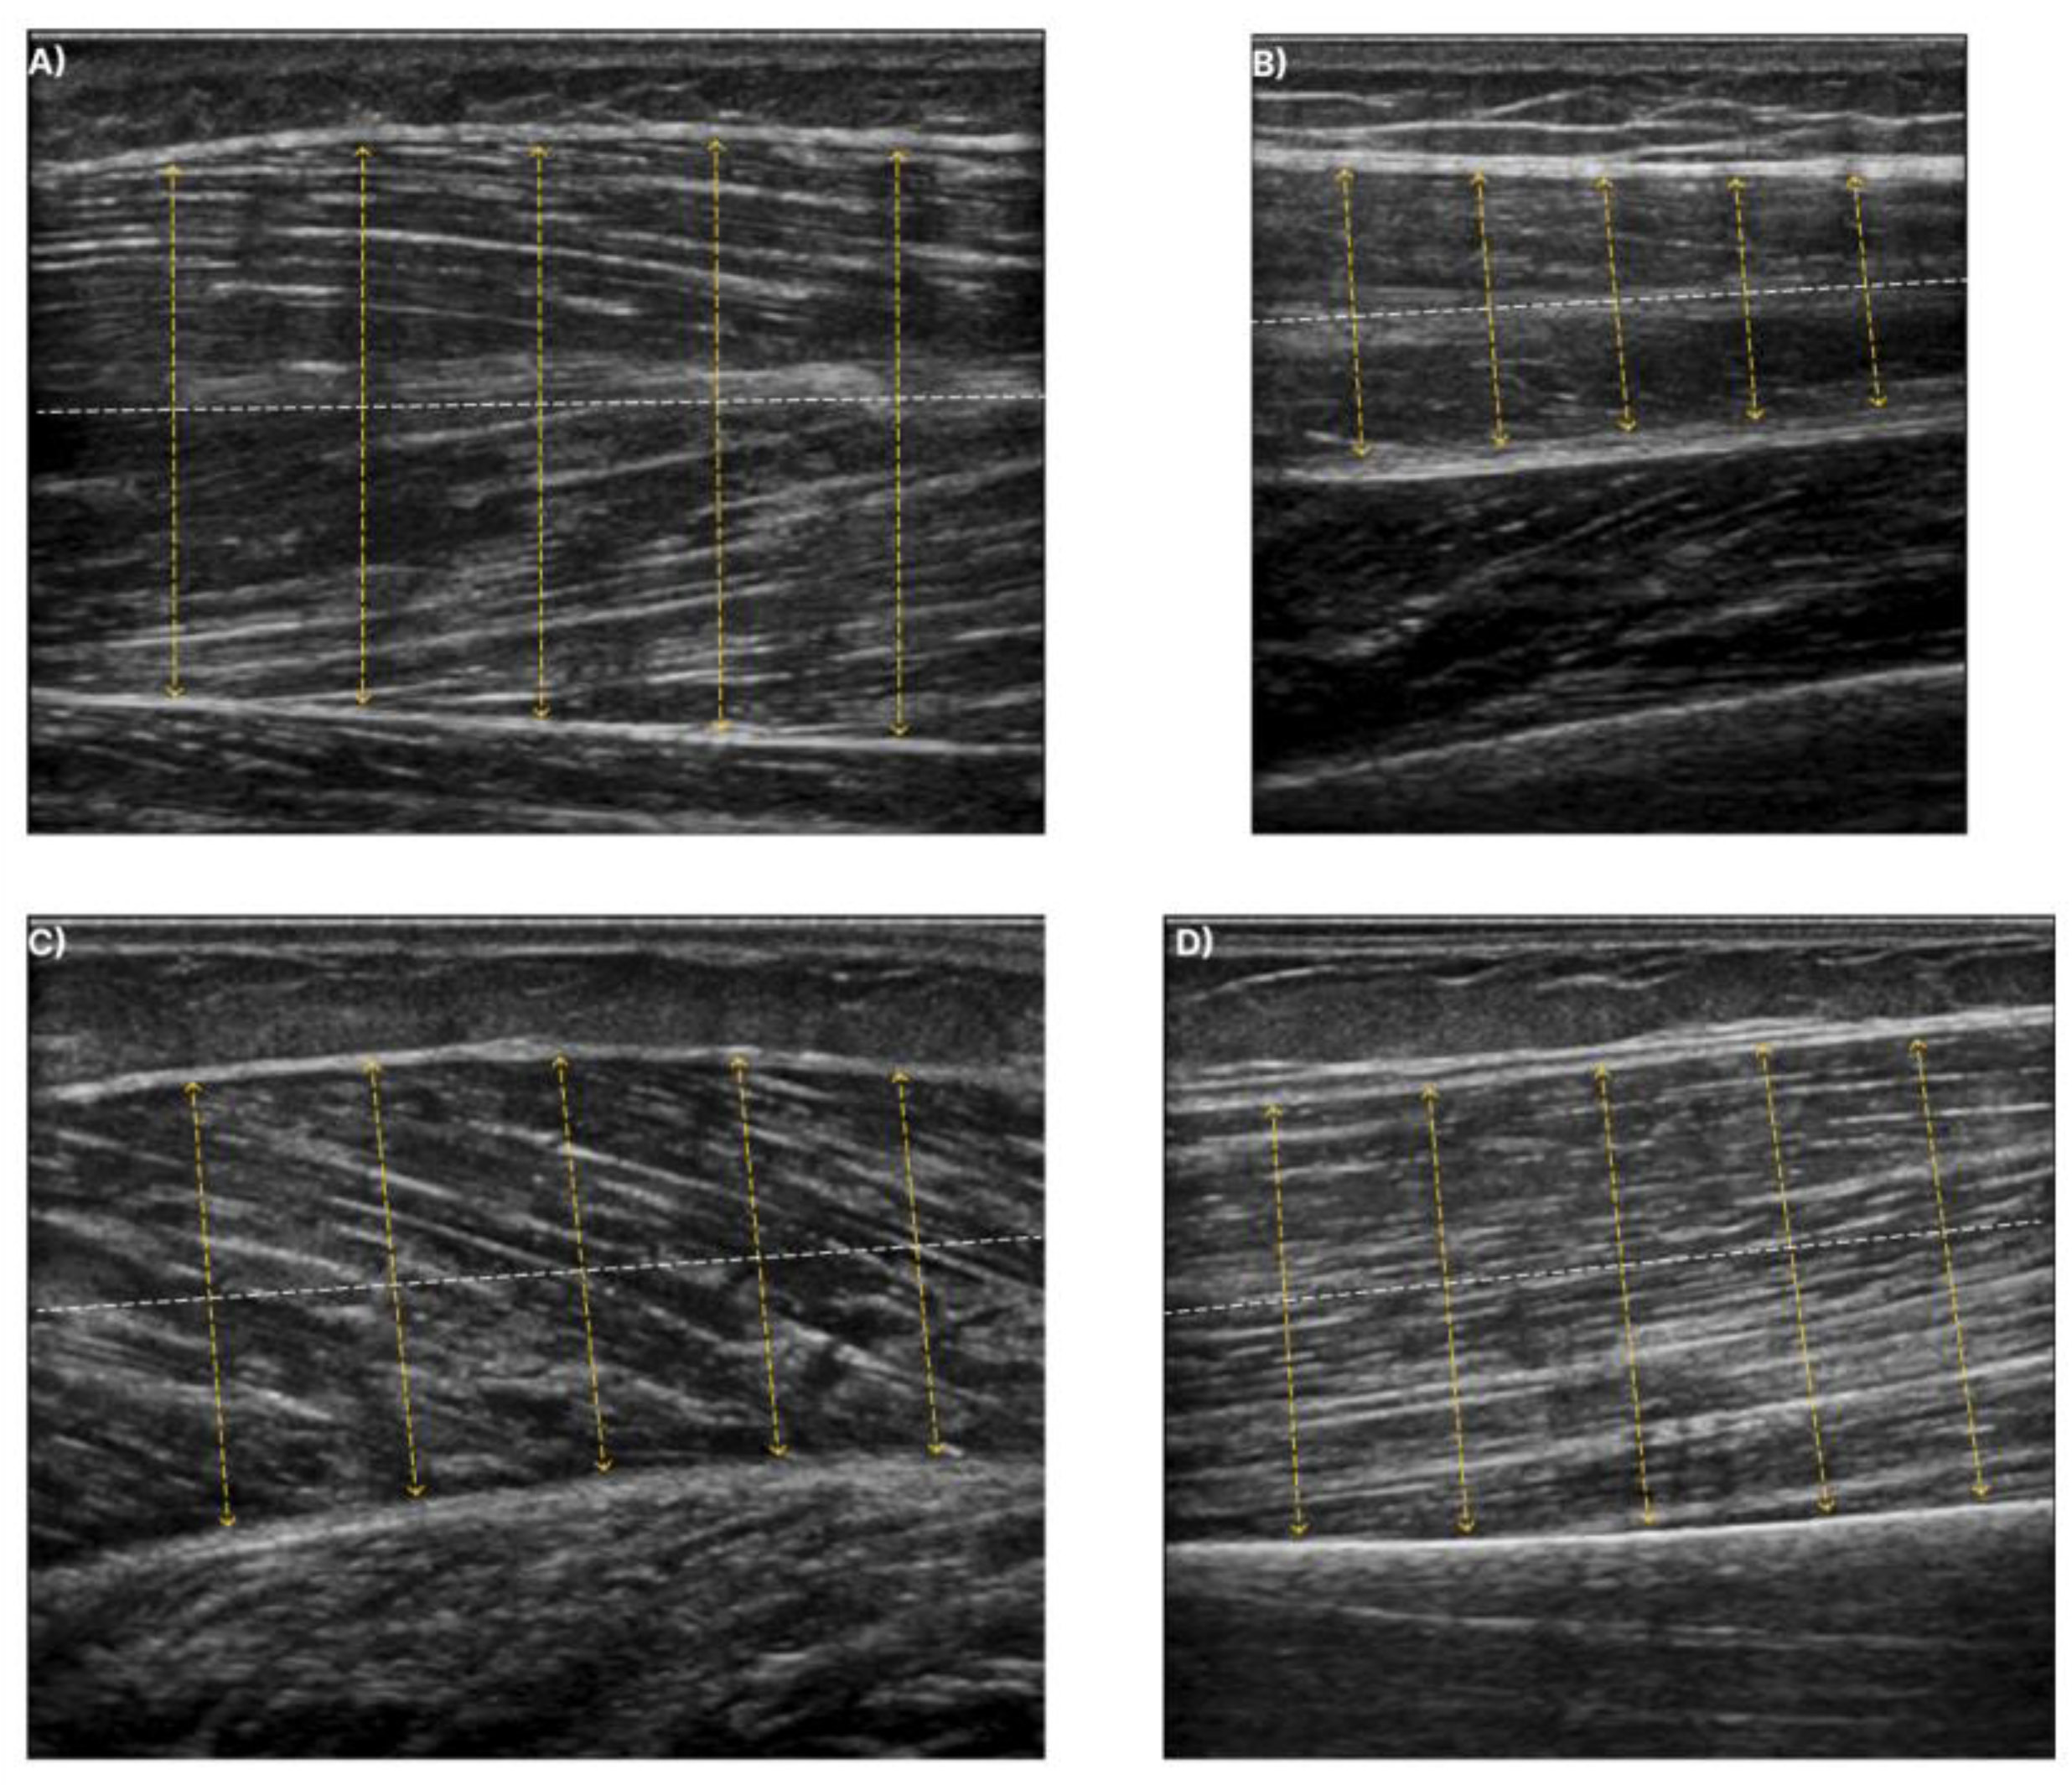

For the muscle thickness (MT) extraction, the pipeline described in [28] was followed. This measurement involves drawing a centre line that lies midway between the superficial and deep aponeuroses. Subsequently, in five evenly distributed points along the centreline, a perpendicular chord is plotted, and the length of this chord is calculated. The muscle thickness is then measured by averaging the distances for all perpendicular chords, as is depicted in Figure 3. Finally, the measurement obtained in pixels is converted into millimetres using a scale factor obtained from the DICOM metadata of the recordings. Although this is not the standard procedure for measuring the MT, it is more robust to user dependence and easier to standardise since it eliminates the variability along the longitudinal axis.

Figure 3. The dashed white line depicts the centreline at each muscle. The yellow lines illustrate the perpendicular chords to the centreline. Muscle thickness is measured from the average distance of the yellow dashed lines. (A) exhibits the T.A., (B) exhibits the R.F., (C) exhibits the GCM, and finally, (D) shows the B.B.